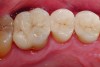

A clinical example of a resin-bonded silica-based ceramic (porcelain laminate veneers) restoration is depicted in Figure 1 and Figure 2.

Fig 1. Preoperative intraoral view of failing composite restorations in the two maxillary central incisors. In addition, the patient was dissatisfied with the esthetics of the maxillary incisors.